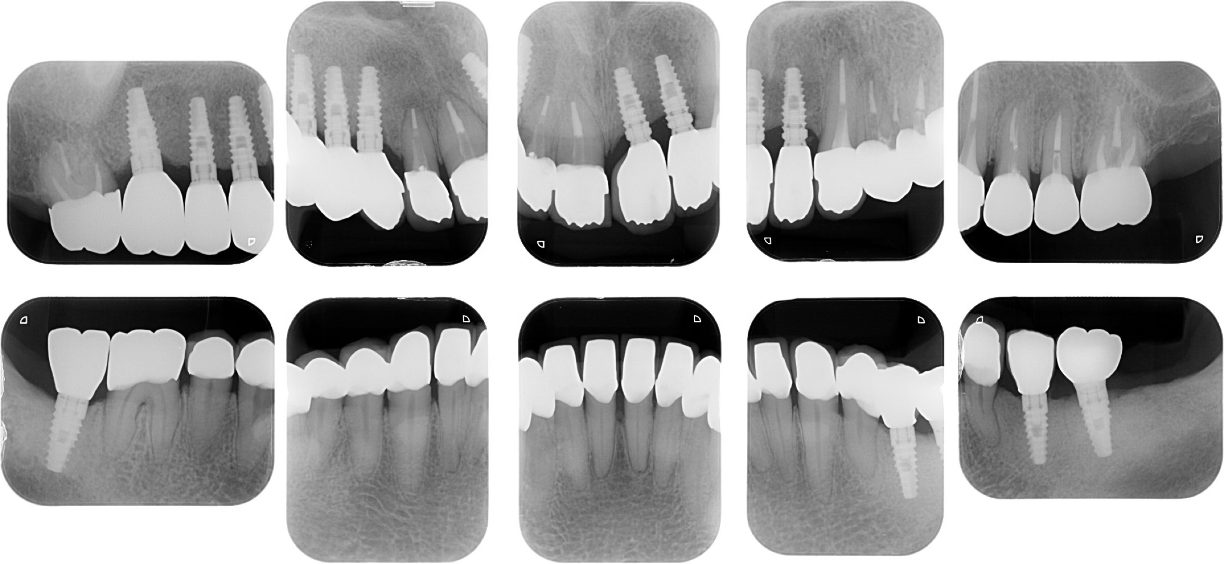

| 主訴 | 全顎治療希望、歯が無いので噛みずらい。定年で時間の余裕出来たので、インプラントで治療して欲しい。 |

| 治療内容 | プラークコントロール不良なため歯周治療を行い、残存歯を極力温存し、欠損部インプラントを施し咬合再構成を行う。 プロビジョナルレストレーションによる咬合関係を模索した後、全顎にわたりセラミックによる補綴治療、その後メインテナンスに移行 |

| 治療費 | 6,470,000円(税込)(インプラントすべて含む) |

| 治療期間 | 1年6ヶ月 |

| 治療回数 | 72回 |

| 想定されたリスク | 食いしばり(パラファンクション)によるセラミックの破折、歯の破折 |